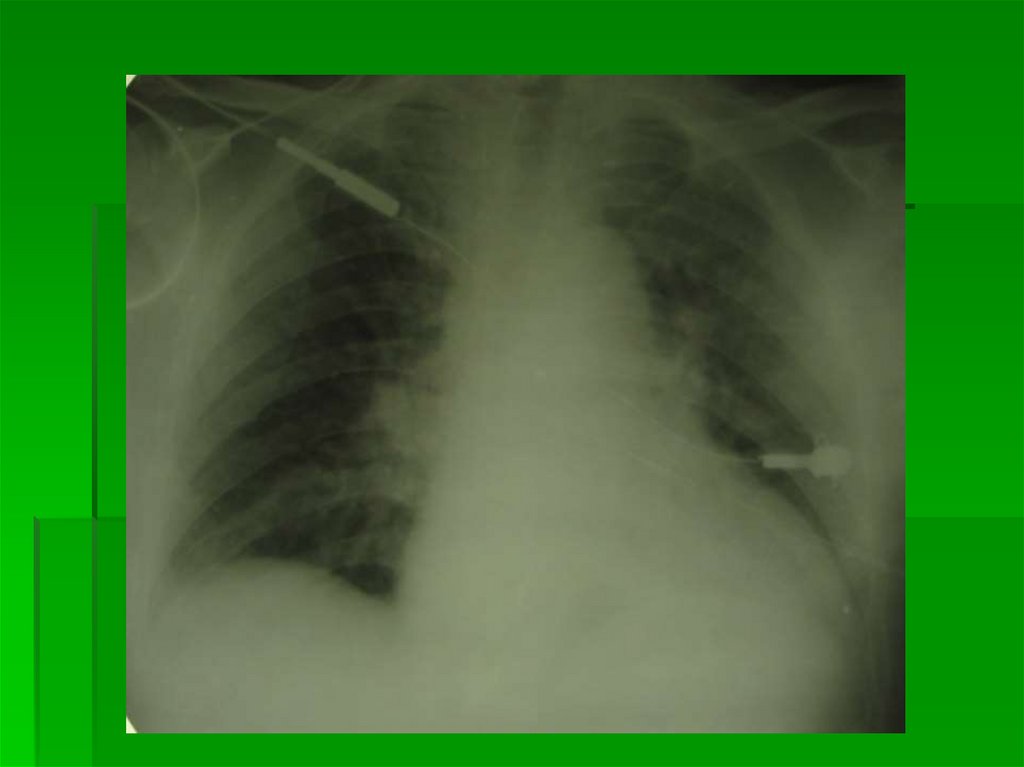

4 степень ЛВГ Альвеолярный

отек легких

P в легочных венах больше 35 мм

рт.ст.

В зависимости от

рентгенологической картины

выделяют:

Сплошной

(массивный,распространенный)

Инфильтративно-подобный

Ацинозно-дольковый

4 степень

Альвеолярный отек легких

Сплошной (массивный, распространенный):

«мокрое легкое», «снимок плохого качества»

Диффузное 2-стороннее, но не зеркальное

затемнение легких

На фоне затемнения корни легких и контуры сердца

практически не дифференцируются

В целом развивается от центра к периферии, но

может захватывать и периферические отделы, в

этом случае интенсивность в центре и на

периферии одинакова

В прикорневых зонах слабо дифференцируются

просветы бронхов (не всегда)

Расширена верхняя полая вена (как проявление

повышения давления в крупных венах)